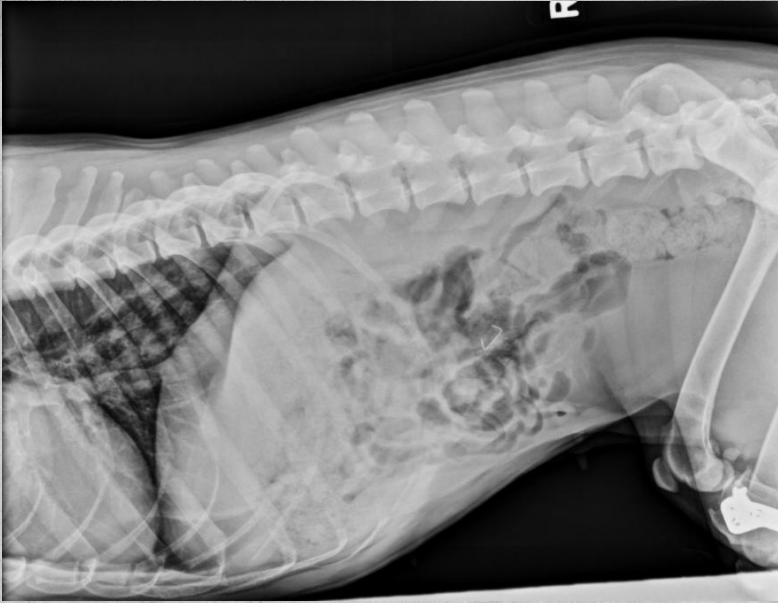

●10 yo female sterilized rottweiler

●Vomiting after every meal for 2 days

● Soft tissue opacity in the area of stomach

● Metal staple in colon

● Metal implant in one knee (from

previous surgery)

● Soft foreign body in stomach – grass,

fabric, wrapping paper

major organs in abdo cavity are hazy and poorly viewed, and lumen of stomach not viewable due to fabric foreign body in stomach.

cecum visible on VD, gas filled bubbles.